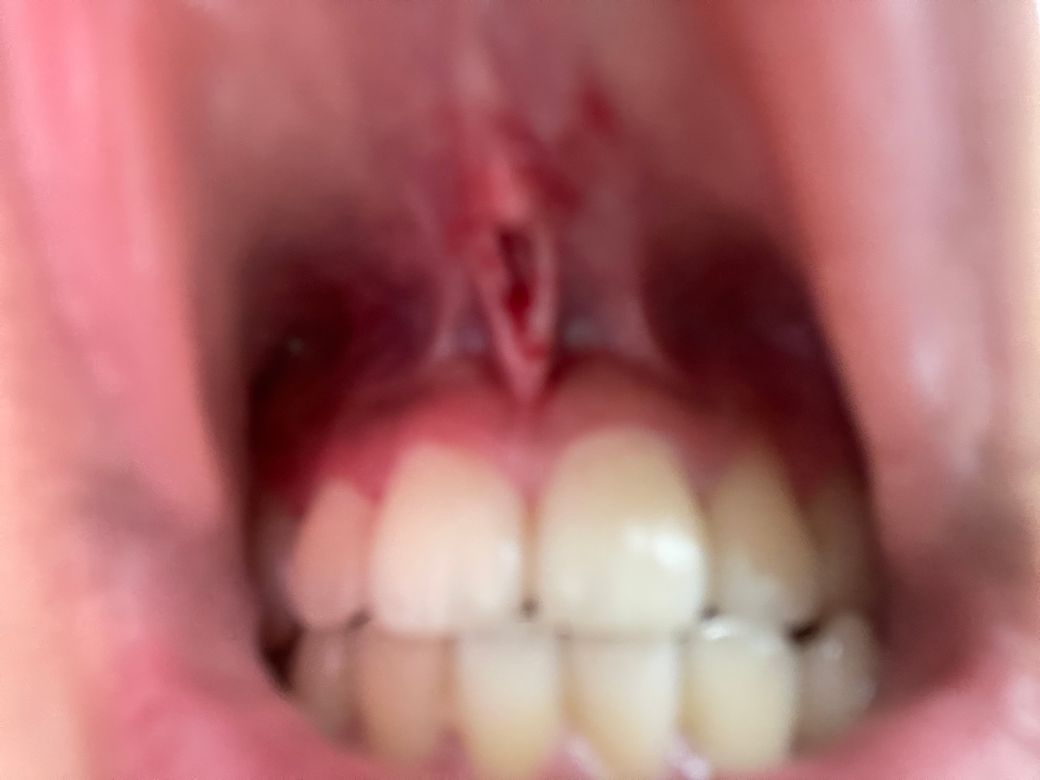

스파링하다가 윗입술과 잇몸 연결하는 부분이 반으로 찢어져서 안피부까지 보이는데 꼭 봉합을 해야만 하는 건가요

심하게 찢어진경우라면 봉합을 해야합니다.현상태는 봉합이 필요로 해보입니다.

설소대 부위의 손상이 발생하신 것으로 보입니다. 해당 부위는 점막 부위이기 때문에 회복이 빠르며 구강 청결을 잘 유지하면서 경과를 지켜보면 따로 봉합을 하지 않아도 원래대로 회복될 가능성이 높습니다. 관련하여서 혹시 모르므로 이비인후과 등 병원에서 진료는 한 번 받아보시길 권고드립니다.

구강내 점막조직은 대생이 매우 잘되는 곳으로 보통 2주정도 지나면 아무는경우가 많습니다.

하지만 창상이 너무 크다면 감염의 위험이 있기 때문에 봉합을 해주는것이 좋을수도 있어요.

정확한 확인을 위하여 치과에서 자세한 진료를 받아보시길 권장 드립니다.